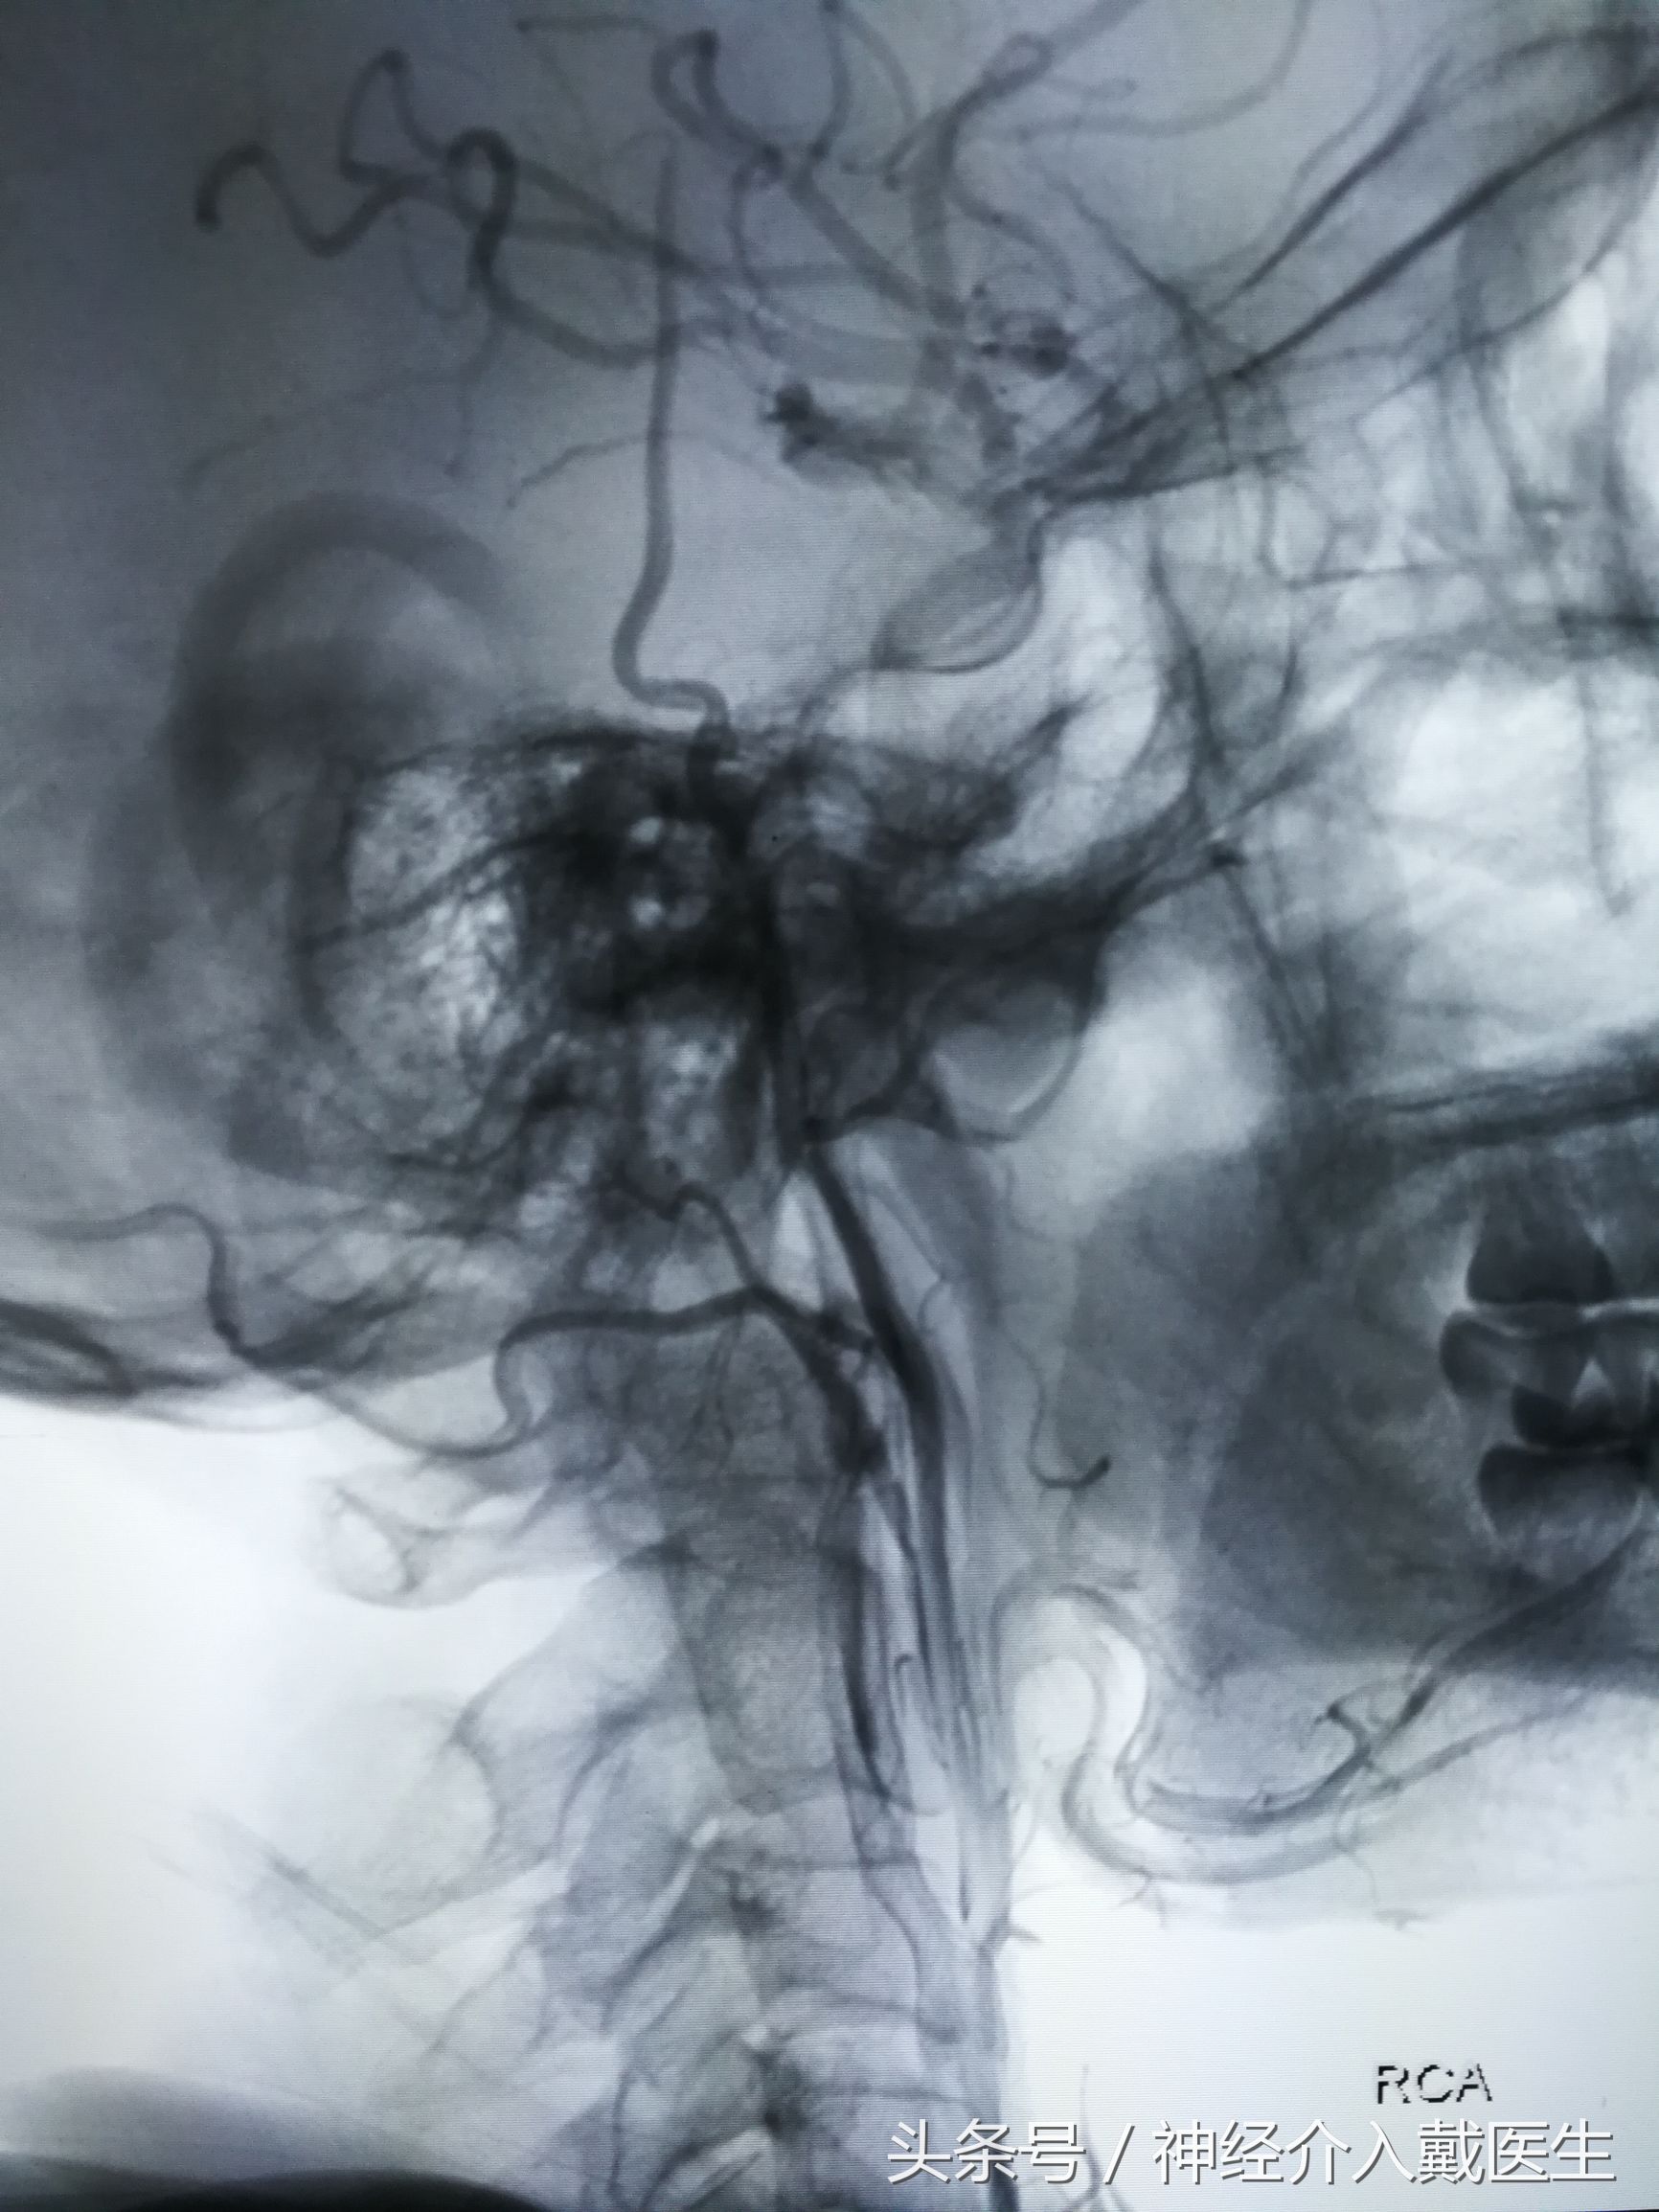

这是颈动脉狭窄经球囊扩张后植入颈动脉支架

手术是在局麻下进行的,术中人神志是完全清醒的,因为手术扩张了颈内动脉,立即改善了脑部血流,术后头晕症状基本消失,没有再晕倒了,只要术后维持吃药,定期复查就可以了。